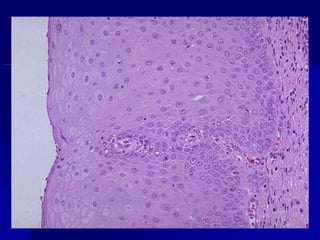

Diferenciación celular

a) Carcinoma

epidermoide de

piel con formación de

queratina.

Epitelio superficial de la mucosa endocervical, que muestra células atípicas, con

su polaridad perdida, con variaciones en el tamaño, forma, disposición y

coloración de sus núcleos. No hay signos de infiltración del estro

Carcinoma escamoso

invasor.

Imagen microscópica a mediano aumento de un carcinoma escamoso invasor.

Obsérvese la presencia de nidos de márgenes irregulares, rodeados por estroma

desmoplásico. Dichos nidos están formados por células atípicas, con diferenciación

escamosa. Focalmente se evidencia alguna disqueratosis. Tinción de H-E,100X.